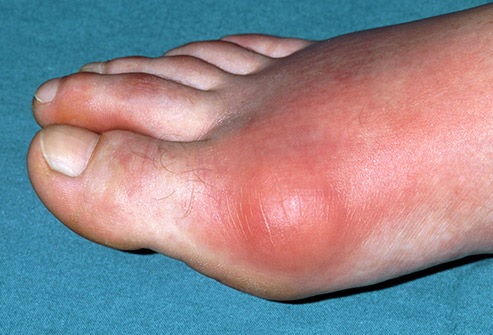

Gout

This condition shows up as a sudden pain and swelling in one of your joints, often a big toe. It’s a form of arthritis caused by a buildup of uric acid in your body. If you take certain medications for high blood pressure, eat red meat and shellfish, and have more than two alcoholic drinks a day, you’re at higher risk. The soda sweetener known as fructose also raises your risk, and so does obesity.